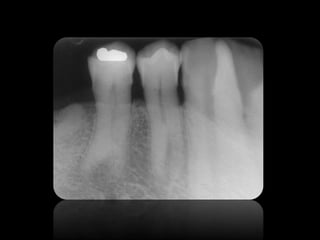

ABSCESO PERIAPICAL